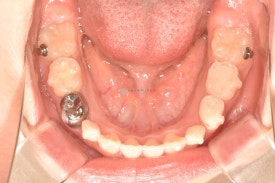

치료 전 - 위아래 심한 공간 부족이 관찰됩니다.

아이는 위 아래 심한 공간부족으로 인한 어린이덧니가 관찰됩니다. 공간부족으로 인해 앞니가 삐뚤빼뚤하게 나왔으며 곧 나올 위 두번째 앞니도 회전되어 맹출이 예상됩니다.

치료 전 - 위아래 심한 공간 부족이 관찰됩니다.아이는 위 아래 심한 공간부족으로 인한 어린이덧니가 관찰됩니다. 공간부족으로 인해 앞니가 삐뚤빼뚤하게 나왔으며 곧 나올 위 두번째 앞니도 회전되어 맹출이 예상됩니다.